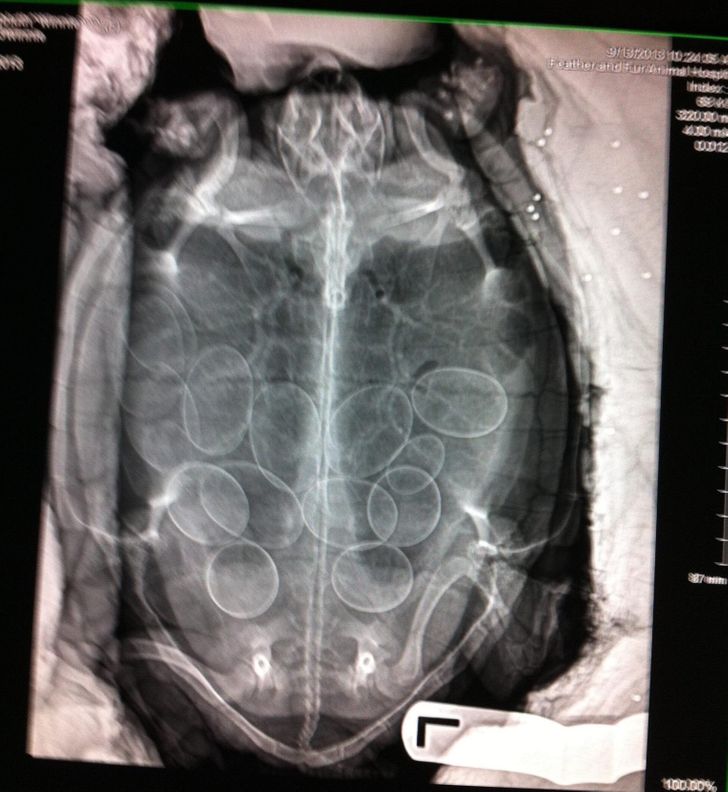

6. Awesome image of a turtle just before it lays its eggs

Illustration de l'article : 14 X-ray images that reveal a hidden story

© DrShellyJ / Twitter